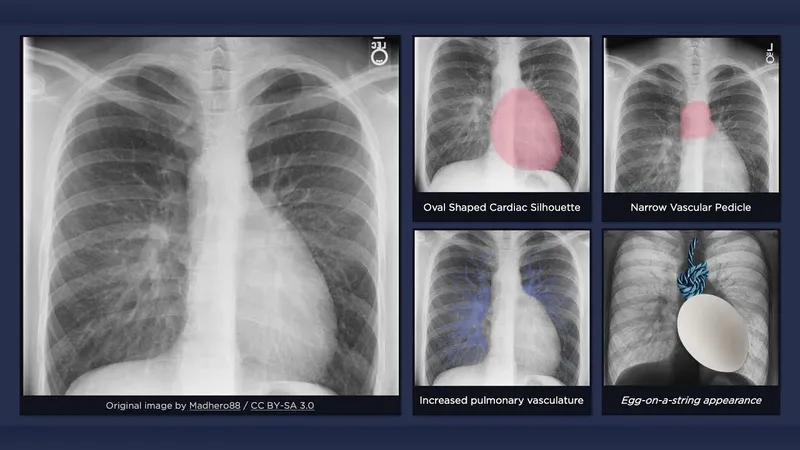

- Key X-Ray Findings:

- TOF: "Boot-shaped" heart.

- TGA: "Egg-on-a-string" appearance.

- TAPVR (supracardiac): "Snowman" or "Figure-of-8" sign.

Classic X-Ray Findings:

- Tetralogy of Fallot (TOF): "Boot-shaped" heart (Coeur en sabot).

- TGA: "Egg-on-a-string" sign.

- TAPVC (Supracardiac): "Snowman" or "Figure of 8" sign.

- Ebstein's Anomaly: "Box-shaped" heart (massive cardiomegaly).

- Classic X-ray findings: "boot-shaped heart" for Tetralogy of Fallot and "egg-on-string" sign for TGA.